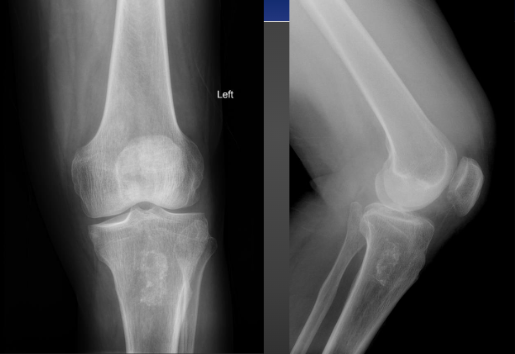

Pedunculated Osteochondroma on X-ray

Sessile Osteochondroma on X-ray

Sessile Osteochondroma in Knee on X-ray

Osteochondroma

-Most common benign skeletal tumor

-75% develop before the age of 20

-Males more commonly affected

-2 types pedunculated & sessile

Most common area for Osteochondroma?

-Knee and the humerus

-Adjacent to growth plates and pointing away from articulations

Imaging Features of Osteochondroma

-Corticomedullary continuity

-Pedunculated (thin stalk with large distal cap that is covered in hyaline cartilage)

-Sessile (Broad based osseous excrescence with possible overlying cartilaginous cap)

-Potential sign of accommodation of adjacent osseous structures or signs of soft tissue irritation